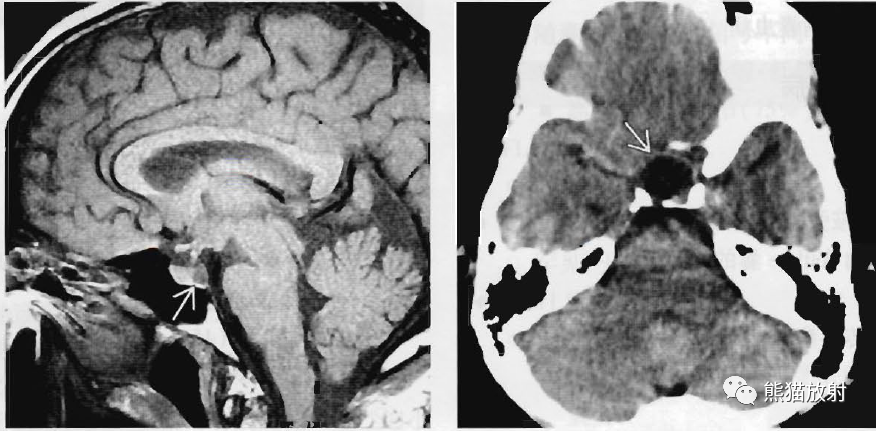

(左) 一例无神经系统症状的头痛患者,矢状位T1WI MR显示所有序列均符合脑脊液信号的小的低信号囊肿(箭)。该病灶为偶然发现,考虑为Rathke裂囊肿。

(右) 轴位NECT显示一脑脊液样低密度的鞍内及鞍上肿块。手术证实为Rathke裂囊肿。